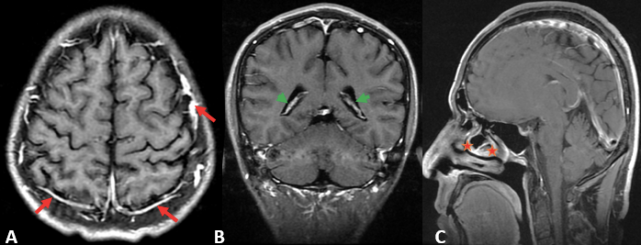

图片

图 5. A. T2 FLAIR 灰白质对比差(红色星和黄色星);脑脊液、玻璃体及病变内囊性成份(自由水)呈明显低信号(绿色箭头);B. 为同层面的 T2 FLAIR 和 T2WI 显示病变周围水肿(结合水)仍呈稍高信号(红色箭);C. 冠状位为 T2 FLAIR